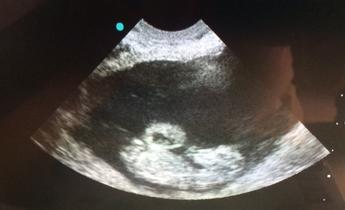

The most advanced form of radiographic imaging available. Whether it is for an emergency situation or pre-purchase exam,  you will be  pleased with the quality, efficiency, and ease of digital imaging. Digital ultrasound is also available for analyzing soft tissue injuries or for reproductive evaluations.

digital radiology and ultrasound